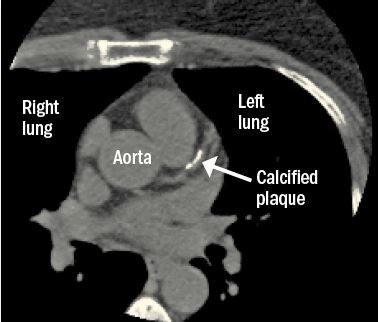

When you look for cancer, you might find heart disease

Screening tests for lung and breast cancer—chest computed tomography (CT) scans and mammograms—may offer clues about a person’s risk of heart disease.